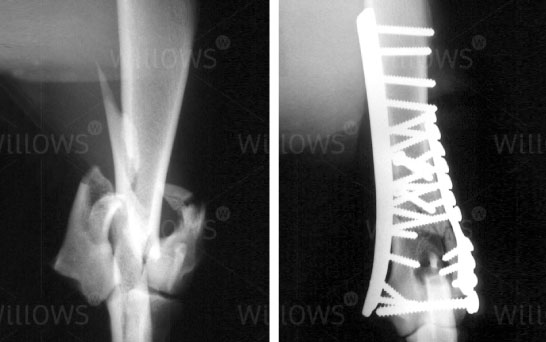

Fig 1: Fracture of the outside (lateral) aspect of the humeral condyle repaired with a plate and screws